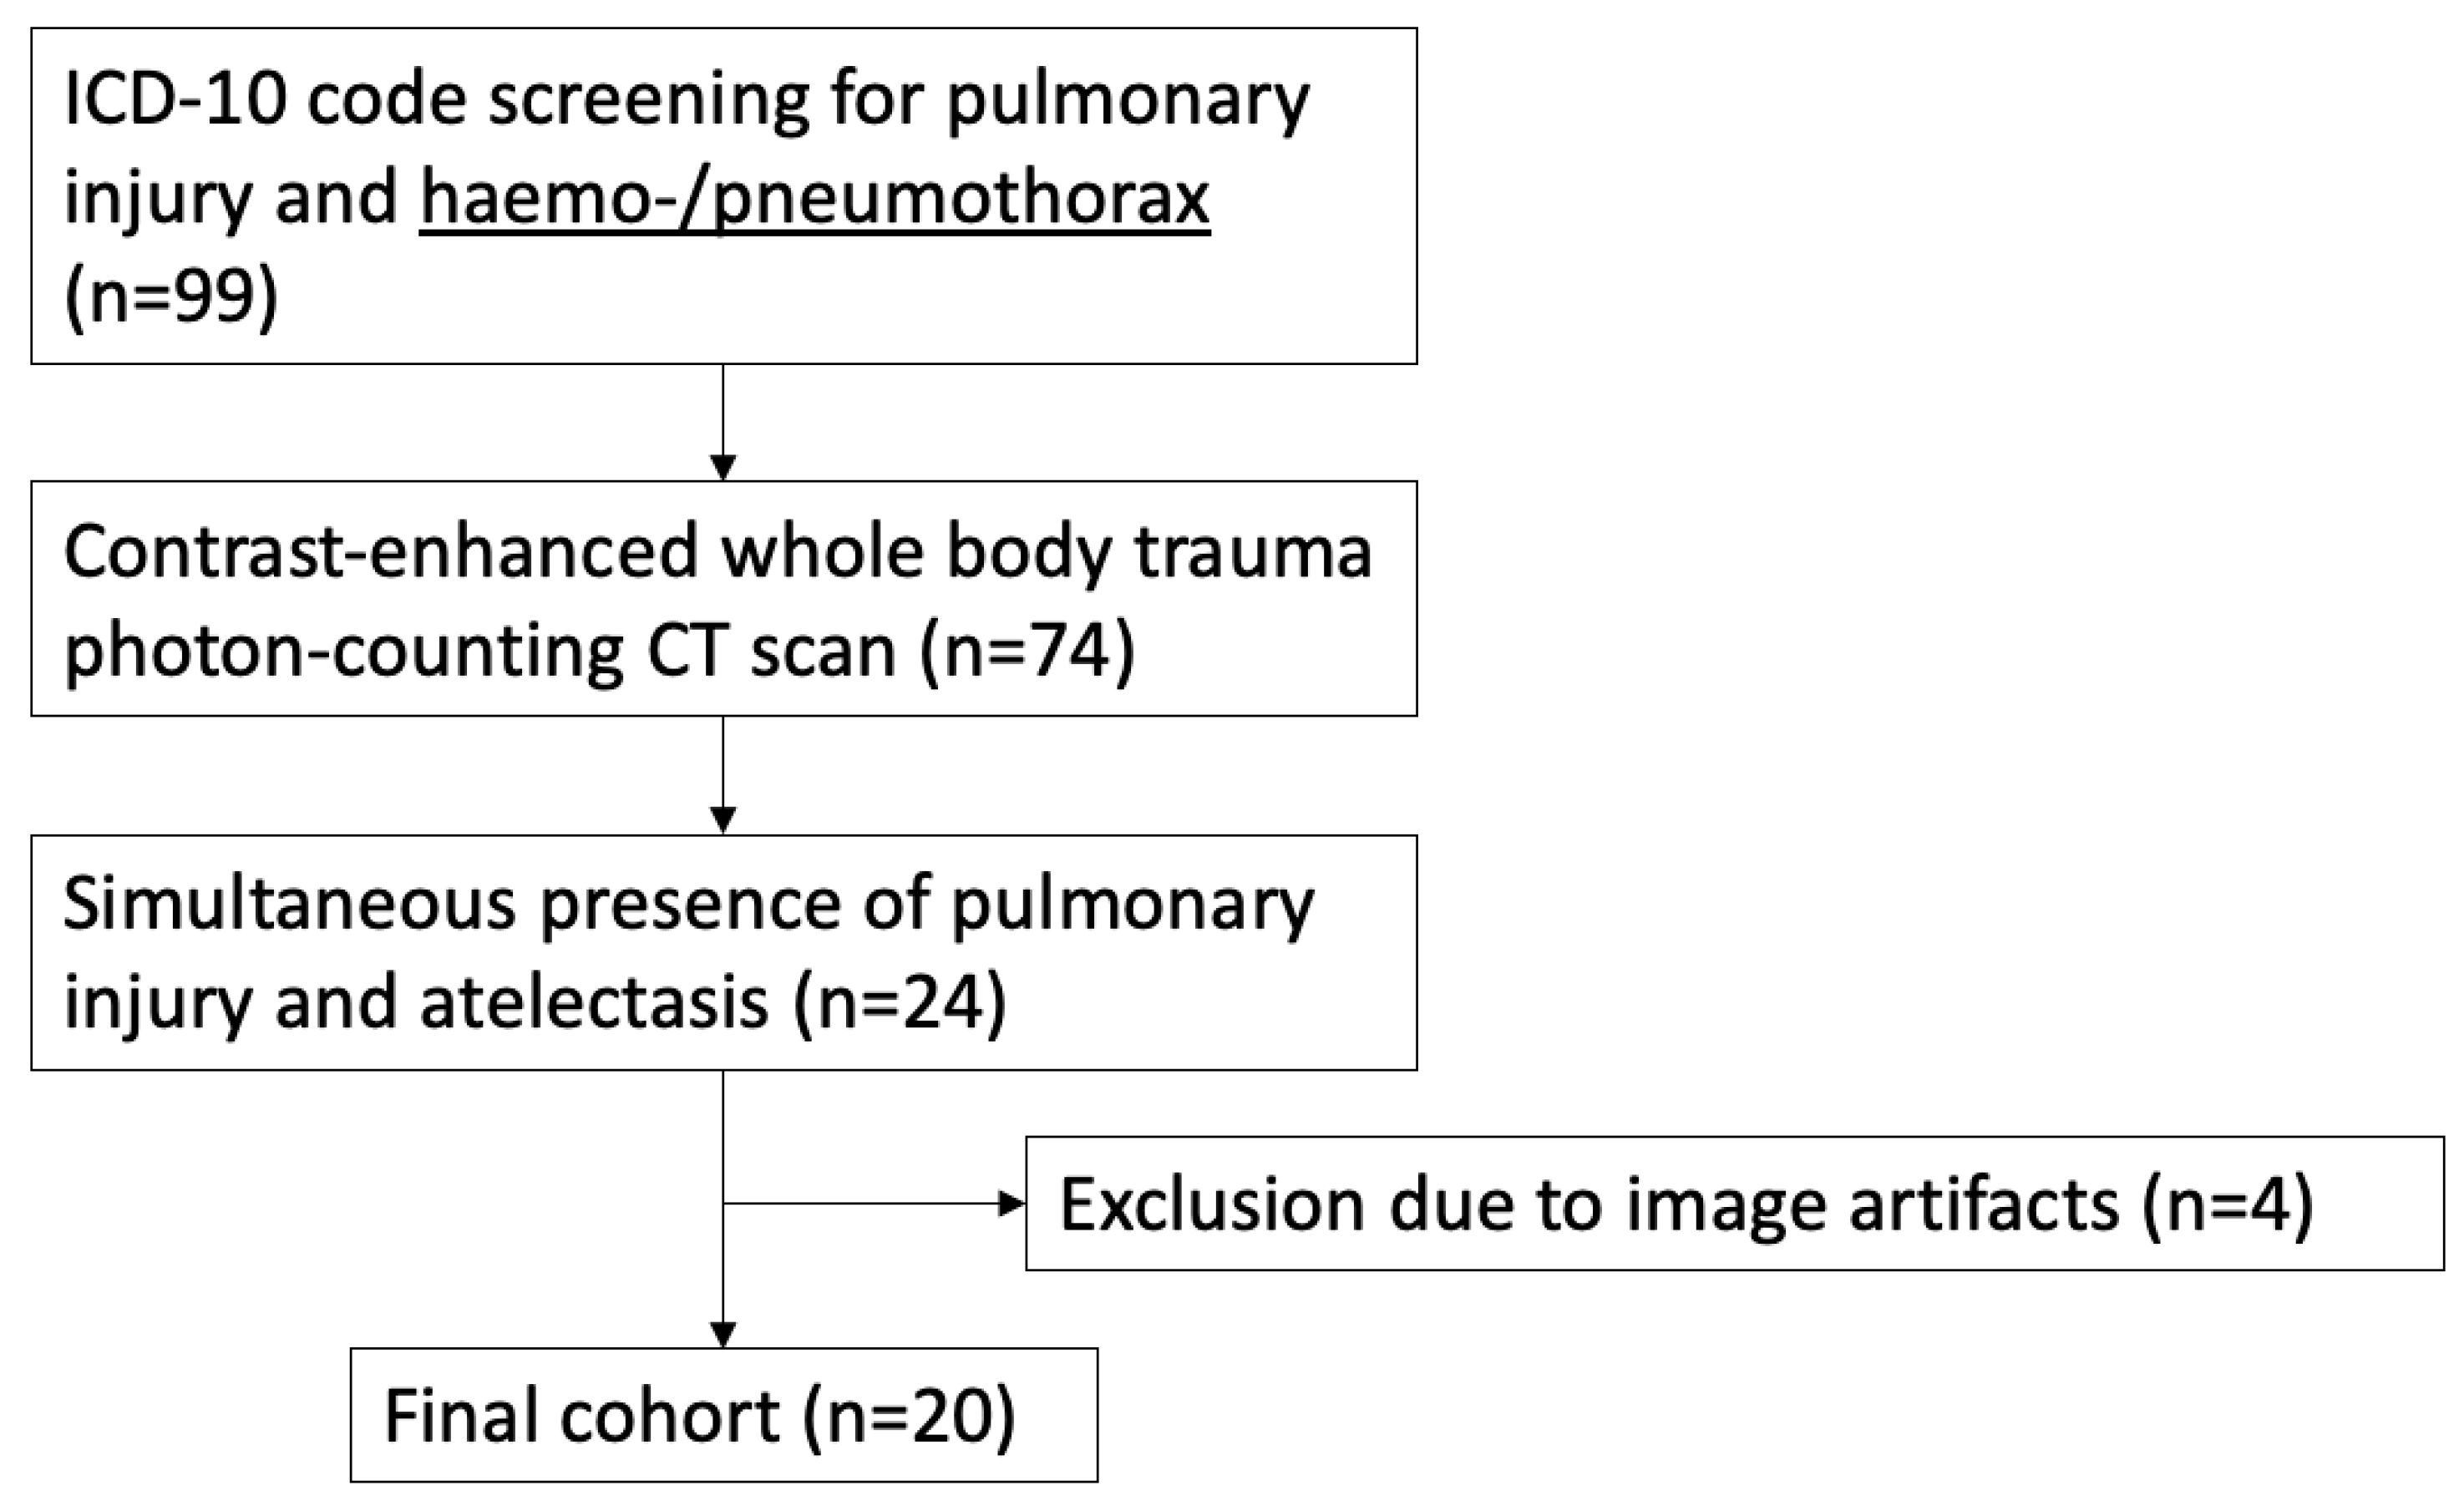

2.2. Study Population